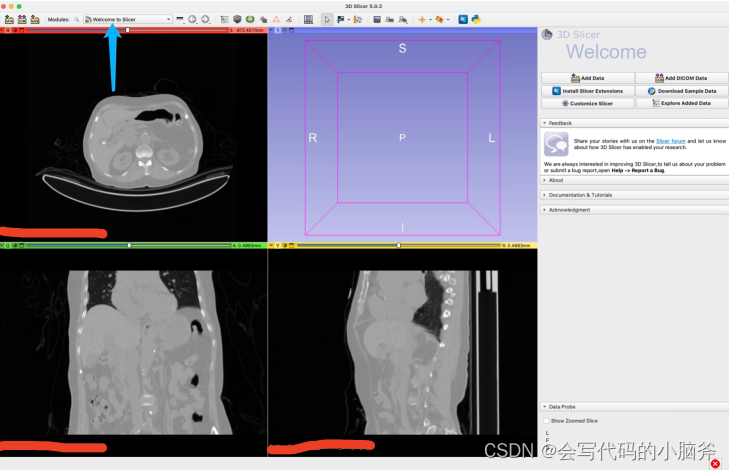

标注:

- 导入数据:

- 开始标注:

- 存储数据